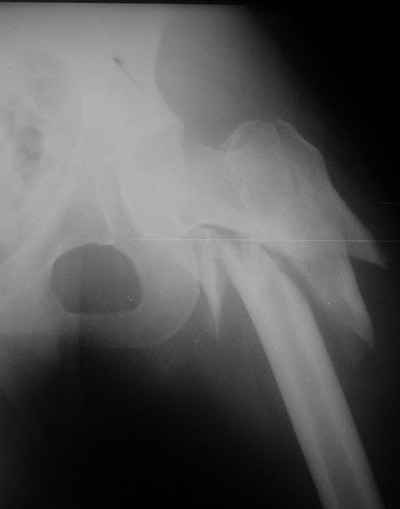

Девушка 21 года 02.10.07 г. пострадала в результате падения с высоты 4-го этажа при пожаре в одном из студенческих общежитий г. Москвы. Получила тяжелую сочетанную травму, в том числе закрытый оскольчатый чрез- и подвертельный перелом левой бедренной кости. Лечилась в одной из больниц столицы. Бедро было фиксировано при помощи скелетного вытяжения. Через полтора месяца после травмы переведена в институт им. Склифосовского. У больной имелись: поддиафрагмальный абсцесс, трахеопищеводный свищ, трахеостома, гастростома, несостоятельность швов раны передней брюшной стенки, укорочение левого бедра на 10 см (рентгенограммы при поступлении - рис 1.). В середине декабря был наложен спицестержневой аппарат, с помощью которого к сегодняшнему удалось устранить укорочение бедра (рис. 2). В течение последних 4-х дней устраняем смещение дистального отломка бедренной кости по ширине. Раны на передней брюшной стенке почти зажили. Температура тела и лабораторные показатели нормальные. Планируем выполнить закрытый остеосинтез левой бедренной кости удлиненным проксимальным бедренным штифтом производства фирмы "Остеомед". Нас смущает, что малый вертел бедренной кости остается значительно смещенным проксимально и кнутри.